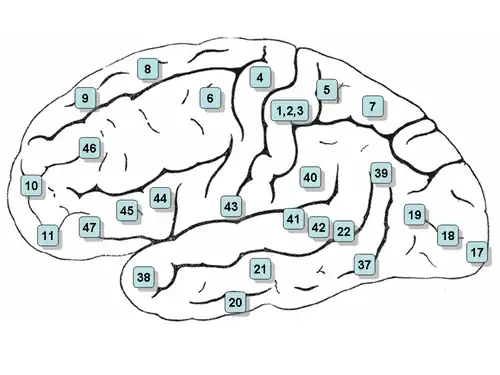

- Vía óptica: a través del núcleo geniculado lateral hacia el área 17 de Brodman.

- Vía auditiva: a través del núcleo geniculado medial hacia las áreas 41-42 de Brodman.

- Señales sensoriales del hemicuerpo y hemicara contralateral: a través del núcleo ventral posterolateral hacia las áreas 1-2-3 de Brodman.

- Cerebelo y globo pálido: a través del núcleo ventral anterior y núcleo vental lateral hacia el área 6 de Brodmann.

- Cuerpos mamilares: a través de núcleo anterior del tálamo hacia la circunvolución del cíngulo.

- Corteza prefrontal: a través del núcleo dorsomedial.[5]